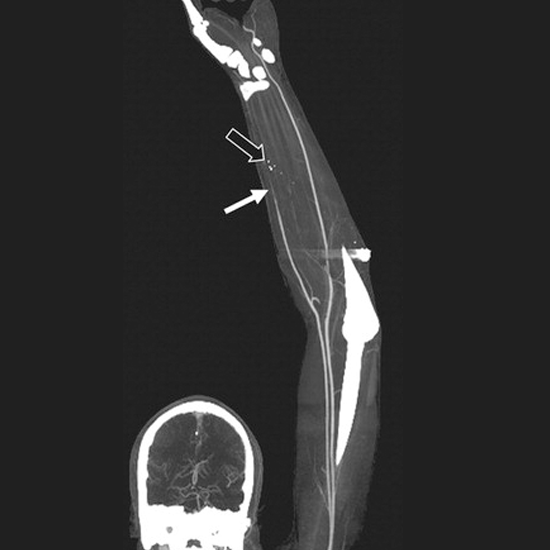

CT Angio Venous Upper Limb (Computed Tomography Angiography of Venous of Upper Limbs). This imaging scan is used to identify the problems in the venous of the upper limb. It is helpful in diagnosing the issues with blood vessels in the upper limb. For the angiography procedure, a contrast media dye is given to the patient to get a detailed picture of blood vessels.

The doctor recommends CT Angio Venous Upper Limb when a patient experiences pain in the upper limbs and the surrounding areas also such as the jaw, chest, neck, and arm. It is used to detect problems such as stenosis, occlusion, vascular malformation, ruptured vessels, congenital disorders, etc. It is also used to diagnose the narrowed and injured blood vessels of the wrist, arms, upper arms, shoulders, and hands.